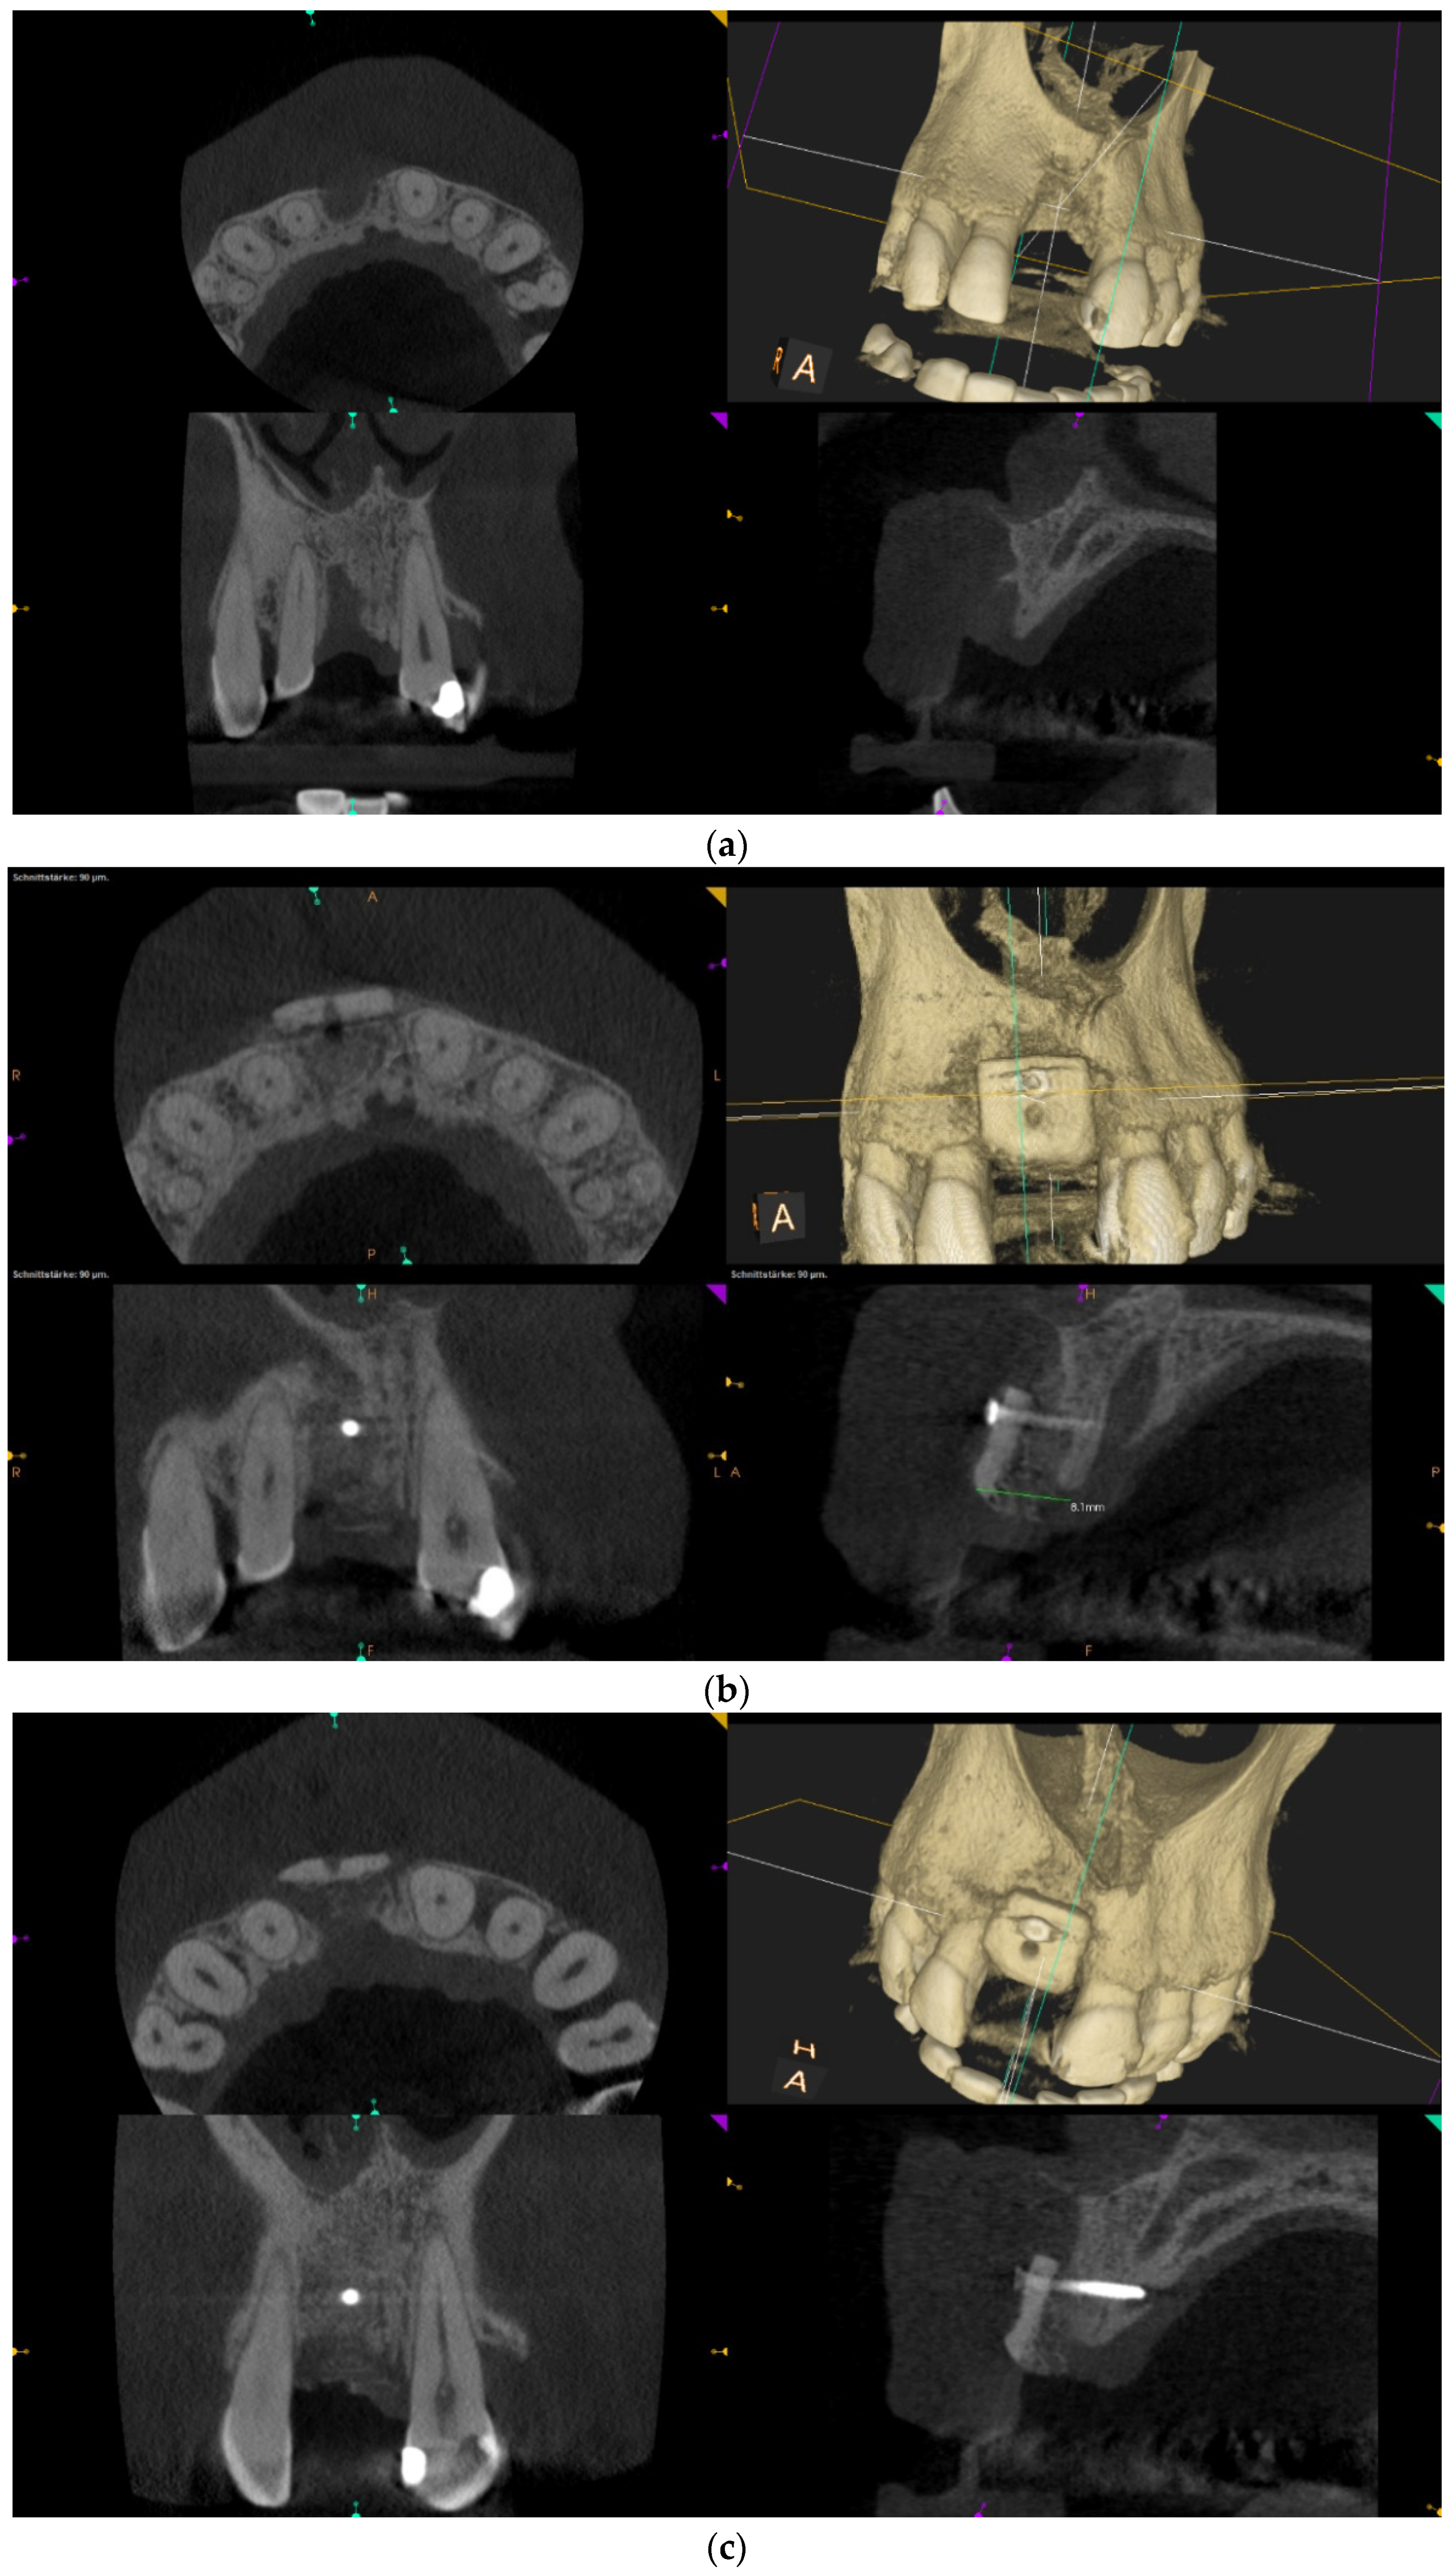

Over-contouring was defined as an over-augmentation of the alveolar process beyond the extent of the adjacent bone level (Figure 1). The reason for over-augmenting the alveolar process is often an anticipated shrinkage of the bone substitution material during the healing phase. Two patients were selected as examples to illustrate the term “over-contouring”. Patient 1 showed a Class III defect in the maxilla, and the alveolar ridge augmentation performed for correction was over-contoured (Figure 2). Patient 2 also showed a Class III defect in the maxilla, but the alveolar ridge augmentation performed for correction remained at the level of the surrounding bone (Figure 3).

Figure 2.

Clinical example of over-contouring. (a) Class III defect with pronounced vestibular deficit and minor vertical deficit. (b) Post-OP: Attachment of a cortico-cancellous allogeneic bone block. Vestibular over-contouring with the cortical plate and vertical over-contouring of the block can be seen. The block protrudes over the limbus alveolaris, i.e., over the bone border of the adjacent teeth. (c) After 5 months: the over-contoured portion of the cortical portion of the block was not resorbed, but part of the cancellous portion of the block was palatally resorbed away. (d) The over-contoured block penetrates the mucosa. The cortical portion is revealed.

Figure 3.

Clinical example of no over-contouring. (a) Class III defect with pronounced vestibular deficit and minor vertical deficit. (b) Attachment osteoplasty with a cancellous allogeneic bone block. The block fits into the contour of the surrounding alveolar process (within the envelope). The lining with the bovine granules is visible (vestibular opaque line). Cranially, the bone block ends at the bone border of the adjacent teeth.

When the massively increased risk of complications of alveolar ridge augmentations due to over-contouring was considered, one may ask why over-contouring was performed at all. Even when comparing the two radiological images in Figure 2 (over-contouring) and Figure 3 (no over-contouring), it seemed questionable why over-contouring should be useful at all. However, the recommendation for over-contouring, especially with autogenous bone material, has been found in numerous literature references.